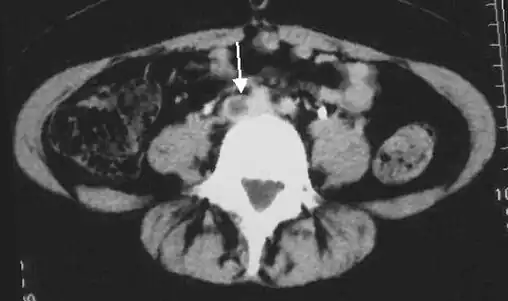

An abdominal CT scan demonstrating an iliofemoral DVT, with the clot in the right common iliac vein of the pelvis

DVT in a leg above the knee is termed proximal DVT (proximal). DVT in a leg below the knee is termed distal DVT (distal), also called calf DVT when affecting the calf,[47][48] and has limited clinical significance compared to proximal DVT.[49] Calf DVT makes up about half of DVTs.[50] Iliofemoral DVT is described as involving either the iliac, or common femoral vein;[51] elsewhere, it has been defined as involving at a minimum the common iliac vein, which is near the top of the pelvis.[19]

DVT often develops in the calf veins and "grows" in the direction of venous flow, towards the heart.[42][103] DVT most frequently affects veins in the leg or pelvis[9] including the popliteal vein (behind the knee), femoral vein (of the thigh), and iliac veins of the pelvis. Extensive lower-extremity DVT can even reach into the inferior vena cava (in the abdomen).[104] Upper extremity DVT most commonly affects the subclavian, axillary, and jugular veins.[11]